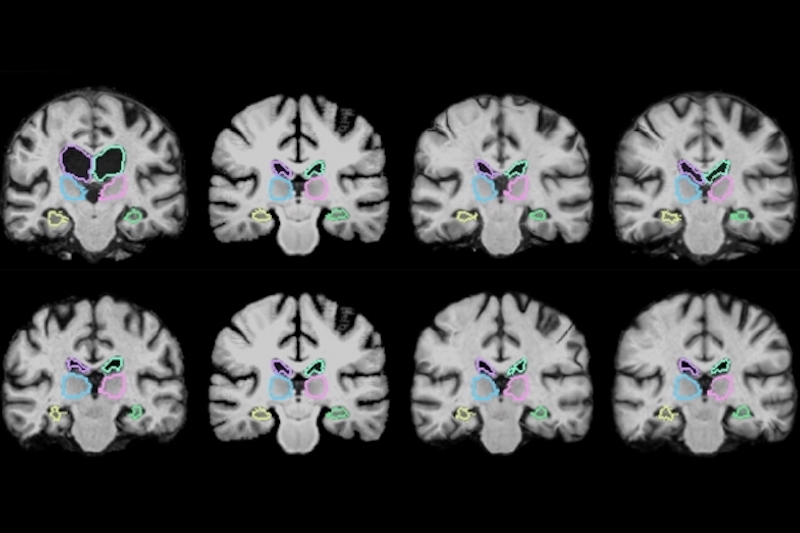

Een nieuw machine learning algoritme van het MIT is wel in staat te leren en kan beeldregistratie hierdoor aanzienlijk versnellen. Het algoritme wordt ‘VoxelMorph’ genoemd en is door de onderzoekers getraind door het duizenden paren van medische beelden van hersenen met elkaar te laten combineren. In totaal zijn tijdens de trainingsfase 7.000 medische beelden geregistreerd. Tijdens dit proces heeft het algoritme informatie verzameld over de wijze waarop de afbeeldingen met elkaar zijn gecombineerd en maakt op basis hiervan een inschatting van de optimale waarden die hiervoor kunnen worden gehanteerd.

De onderzoekers hebben VoxelMorph tijdens een test 250 medische beelden van hersenen met elkaar laten combineren. Hieruit blijkt dat het algoritme dankzij zijn training in staat is medische beelden in ongeveer twee minuten te registreren op een regulier computersysteem zonder grafische kaart. Indien een grafische kaart wordt ingezet kan het proces zelfs in minder dan een seconde worden uitgevoerd. Dit terwijl de nauwkeurigheid van VoxelMorph niet onder doet voor die van traditionele beeldregistratiesystemen.